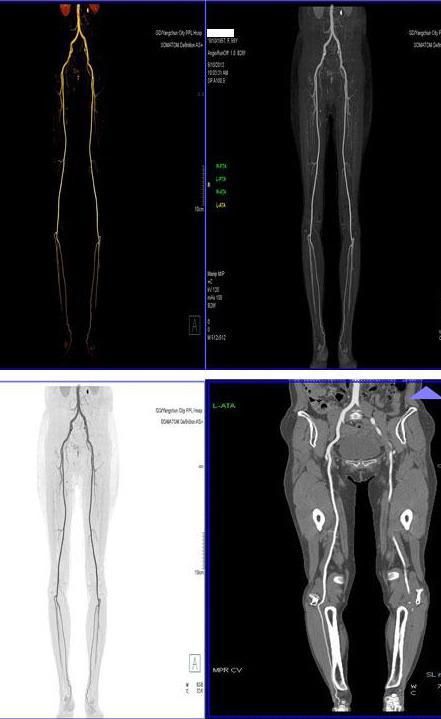

二、多層螺旋CT頭頸部及體部血管成像技術:

該機掃描覆蓋範圍廣、時間短,多種後處理分析軟件能顯示各血管細小分支,可以清晰顯示動脈瘤、動脈夾層、血管畸形、血管狹窄及動脈粥樣硬化斑塊等,适用于頭頸部血管成像、肺動脈成像、胸腹部血管成像及四肢血管成像。

5、下肢動脈血管成像: